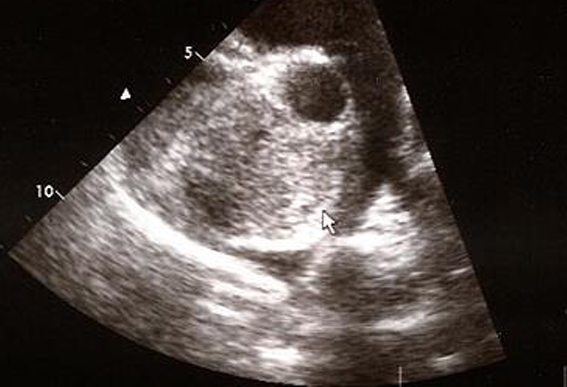

Radiography

• 처음에 먼저 LA, LV 확장(enlargement)부터 발생

• R-L shunt 근처까지 병이 진행되면 dAo & mPA 확장

• Aorta에 비해 상대적으로 벽이 덜 두꺼운 mPA 가 꽈리 모양으로 enlarged됨